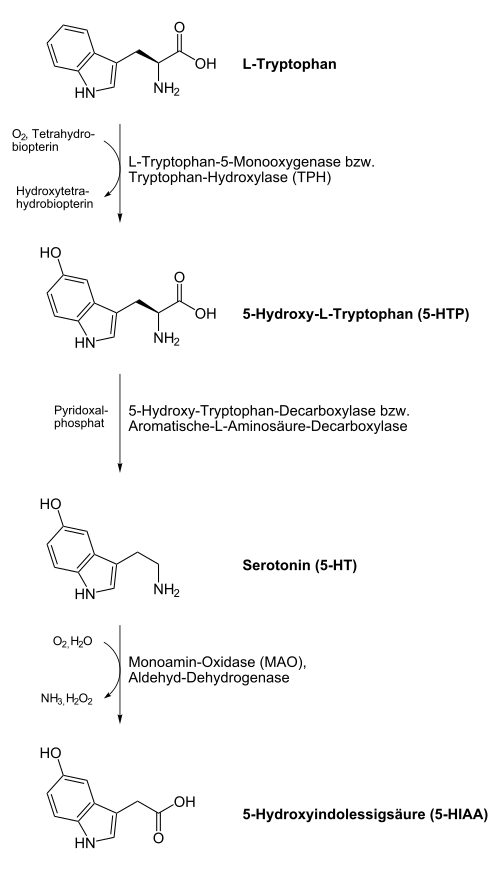

Biosynthese

Beim Menschen und bei Tieren wird Serotonin aus der Aminosäure L-Tryptophan in einer Zwei-Schritt-Reaktion unter Beteiligung der Enzyme Tryptophanhydroxylase und Aromatische-L-Aminosäure-Decarboxylase aufgebaut. Im ersten Schritt entsteht als Zwischenprodukt die nicht-proteinogene Aminosäure 5-Hydroxytryptophan (5-HTP). Im zweiten Schritt erfolgt eine Decarboxylierung zum Endprodukt Serotonin. Der wichtigste Produktionsort sind die enterochromaffinen Zellen der Darmschleimhaut. Von hier aus wird das produzierte Serotonin über die Blutplättchen transportiert. Eine Passage der Blut-Hirn-Schranke ist jedoch nicht möglich, sodass Serotonin auch im Zentralnervensystem produziert werden muss. Den Stellenwert der neuronalen Serotoninproduktion zeigt die Anwesenheit einer zweiten paralogen Tryptophanhydroxylase im Gehirn, die bereits vor der Entwicklung der Wirbeltiere durch Genverdopplung aus der ersten Isoform hervorging.[42]

Abbau

Das Serotonin der Nervenzellen wird nach seiner Freisetzung in den synaptischen Spalt aktiv mit Hilfe des Serotonin-Transporters (SERT), eines Transportproteins, rückresorbiert und wiederverwertet. Das aus den enterochromaffinen Zellen produzierte Serotonin wird rasch nach seiner Freisetzung über das gleiche Transportprotein in den Epithelzellen der Darmschleimhaut und in den Thrombozyten gebunden. Der Abbau von Serotonin erfolgt vorrangig über das Enzym Monoaminooxidase (MAO) vom Typ A und in einem deutlich geringeren Maß über MAO Typ B. Das Produkt 5-Hydroxyindolylacetaldehyd wird von der Aldehyd-Dehydrogenase weiter zu 5-Hydroxyindolylessigsäure (5-HIES) abgebaut. 5-Hydroxyindolylessigsäure, die im Urin nachgewiesen werden kann, ist das Hauptausscheidungsprodukt von Serotonin.